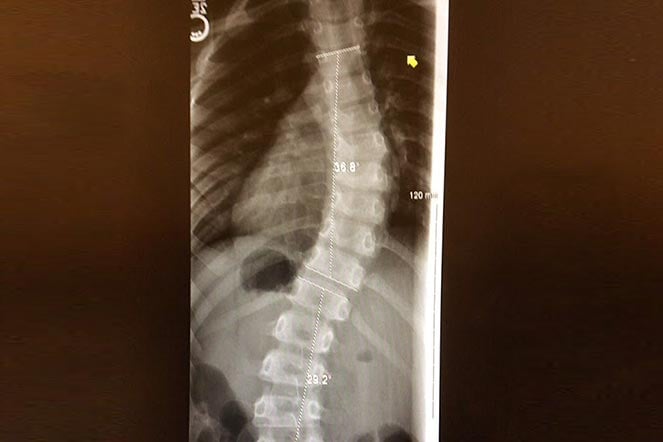

scoliosis patient spine X-ray

An X-ray shows Julia’s curved spine.

A 39-degree S-curve threatened to progress rapidly, putting her on the brink of surgery rather than bracing. Their path to specialized care came through an unexpected connection: Julia's dad had recently bought a business from a Shriner (a member of the philanthropy that supports Shriners Children's), who recommended Shriners Children's Northern California.

Orthopedic surgeons Jenny Boakes, M.D., and Debra Templeton, M.D., discussed potential future surgical interventions like spinal fusion once she was fully grown. However, aligned with her parents' wish to avoid surgery, the immediate plan focused on bracing. Her orthotics team, Greg and Sunny, crafted Julia's braces. Thanks to Julia’s willingness to wear her brace and her team’s monitoring expertise, Julia avoided surgery entirely. Her curve significantly improved, stabilizing at 25 degrees.